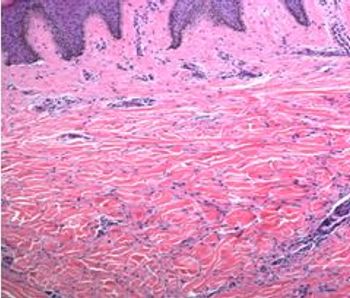

Dermatofibromas may present as papules or nodules that are elevated or slightly depressed. Suspected etiology includes skin injury such as insect bites.